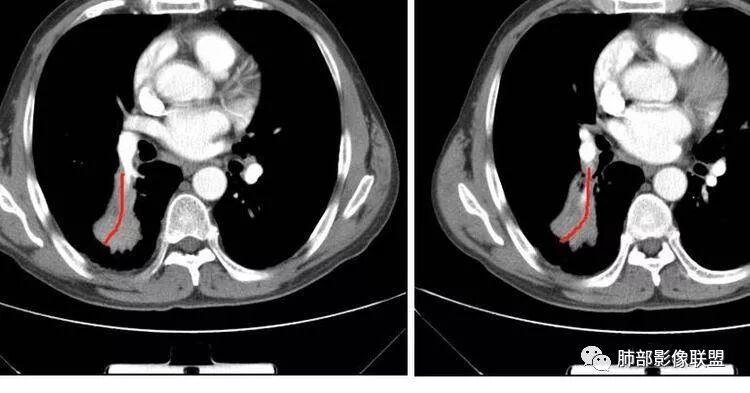

南边:紧贴着斜裂过来的一个病灶,它的特点是:外围大,内带小。它整个下叶背段体积与对侧相比稍微缩小一点,但是缩小地不是很厉害。外支朝前下走了,仔细看血管,肺动脉走行自然,直达远端。远端实变区是肉芽肿成分,稍微有一点低密度,没有明显坏死,稍微有一点点坏死。而且附近有很多卫星灶,附近很多斑片影,有一些明显有气道壁增厚,细支气管炎的特点,还有就是下叶其他段很多斑片状影。换个角度,第一如果是肺癌,刚才看到PET-CT提示肺癌伴阻塞性肺炎,这个是不符合的。第二如果是肺癌阻塞性肺炎,近端血管肺动脉走行不会那么自然集聚的,这个是不符合的。理由是:如果这个病灶是肺癌,那么明显属于中央型肺癌,中央型肺癌的特点是近端大,远端小,近端是一个肿块,远端阻塞,远端阻塞是阻塞性炎症或者不张,它应该体积缩小,斑片状实变,不会这么密实。刚才有老师提到支气管,这个片有缺陷的地方,给的图像好像那层,如果把其他图像拿开再重叠一下。

南边:这个肺门区,11区和7区都有一些淋巴结,淋巴结的形态不是类圆形,而是梭形的。这个病灶给的图比较少,个人倾向,第一强化非常均匀,肉芽肿性病变;第二,里面血管走行非常自然,远端大近端小,倾向炎性,特别是下面还有斑片状影,非阻塞远端,支气管远端病灶下叶背段,其他段也有,所以我倾向炎性;另外,它里面整个走行符合支气管树爬行征,我倾向结核可能,首先我定在炎性,其次有没有结核的可能。

右肺下叶背断肿块,外围大,内带相对狭长         远端有膨隆,边缘模糊、凹凸不平         血管走形自然,病灶近端支气管通畅,沿支气管树蔓延         周边有多发病灶,多为磨玻璃密度且边界不清。

轻度强化         PET-CT:SUV 7.5,高摄取